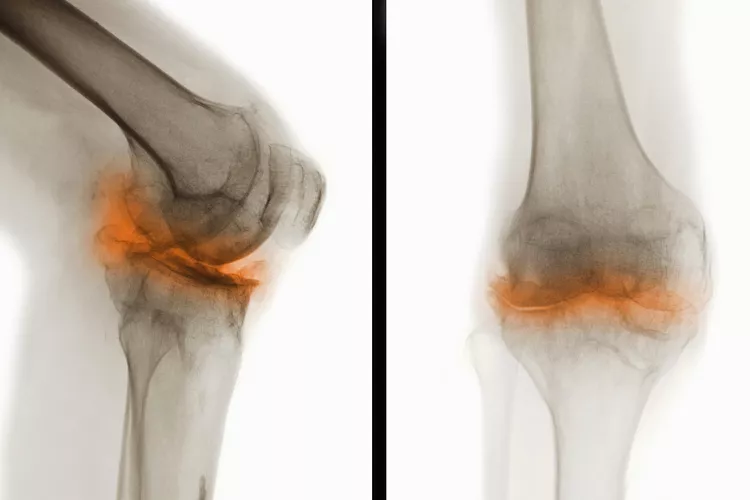

骨關節炎(Osteoarthritis, OA),一種常見的慢性關節疾病,主要特征是關節軟骨退化和關節邊緣骨質增生。隨著病情進展,骨關節炎不僅會導致關節疼痛和功能受限,還可能引發一系列并發癥,影響患者的整體健康和生活質量。

在骨關節炎(OA) 中,覆蓋骨頭末端并幫助骨頭相互滑動的光滑軟骨會逐漸磨損。這會導致骨頭相互摩擦和磨擦。

骨關節炎是一種慢性疾病。骨關節炎無法治愈。一旦軟骨破裂,它就不會自行再生。隨著時間的推移,您可能會因患有骨關節炎而出現其他問題或并發癥。

關節損傷

可能的問題包括:

- 脊柱神經受到擠壓(后天性脊椎滑脫或脊椎狹窄)

- 關節感染,但這種情況很少見

- 關節周圍的肌腱和韌帶變薄或撕裂,導致關節不穩定

- 軟骨溶解癥,軟骨突然完全破裂,導致關節內組織松散

- 應力性骨折,由于反復的壓力而緩慢地在骨頭上形成細微裂縫

- 貝克囊腫是膝蓋后面的軟性充滿液體的腫塊。它們大多無痛,但會壓迫血管導致腿部腫脹,或破裂并引起疼痛